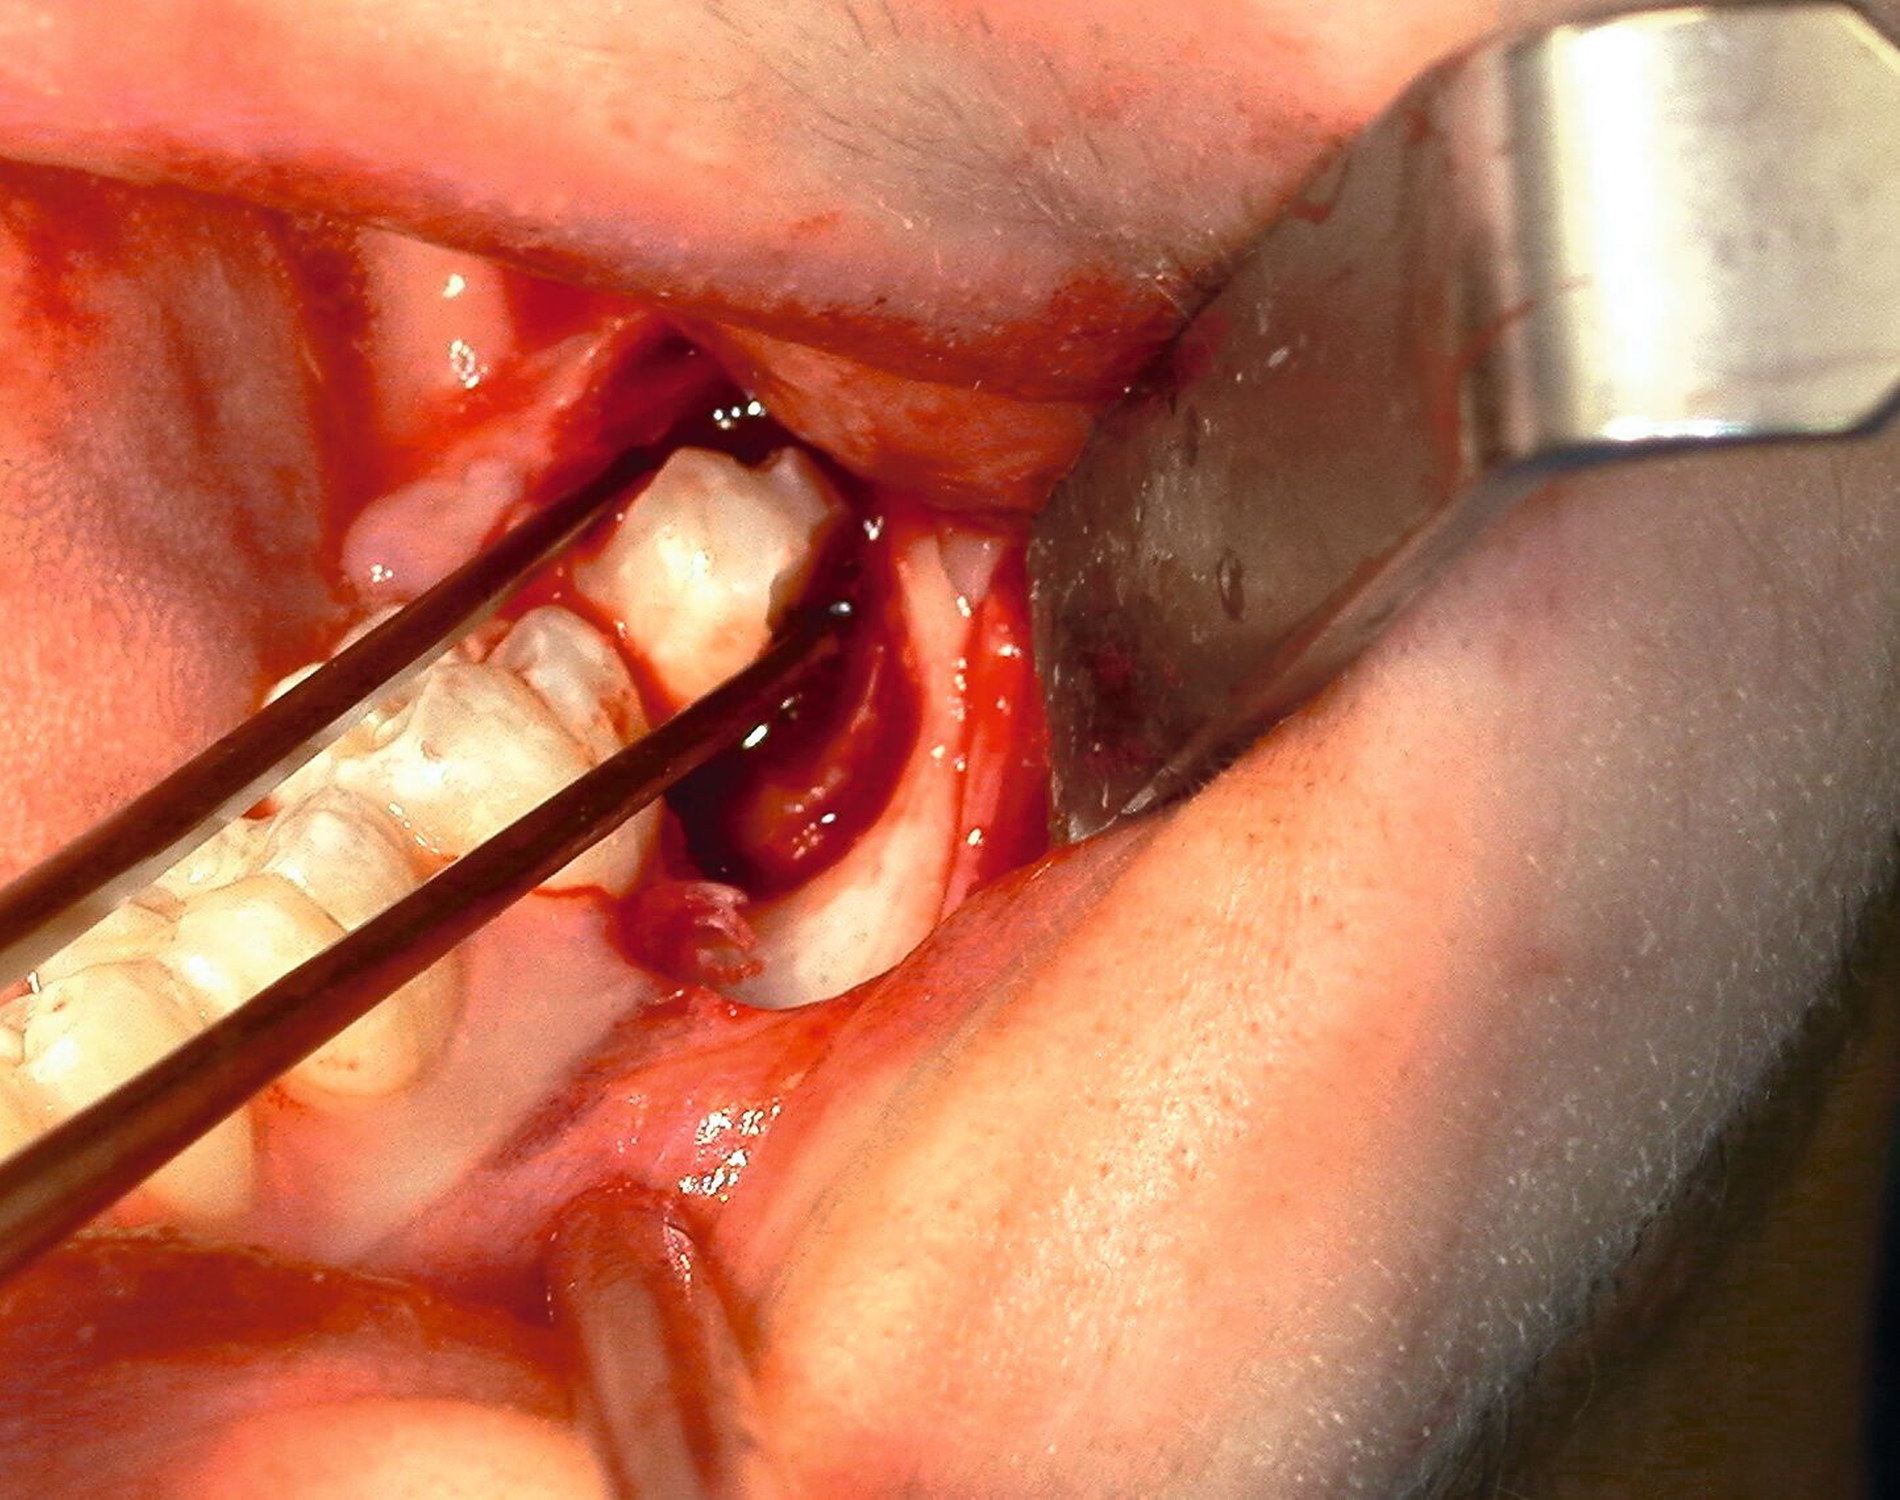

Nach Freilegung des Knochens kann ein Wundhaken nach Langenbeck eingesetzt werden sowie ein Bohr-Raspatorium zum Schutz des N. lingualis subperiostal lingual [Gutwald et al., 2019]. Unter Verwendung eines rotierenden Instruments (Kugel- und Lindemann-Fräse) oder Piezochirurgie wird der Knochen im Bereich der Zahnkrone abgetragen und diese freigelegt (Abbildung 8). Danach kann der Weisheitszahn vorsichtig mithilfe eines Bein‘schen Hebels anluxiert oder, falls dies noch nicht gelingt, mittels einer Lindemann-Fräse geteilt werden. Dabei wird am größten Kronendurchmesser die Krone mit der Fräse abgetrennt und die Wurzel anschließend separat entfernt (Abbildungen 9 und 10) [Gutwald et al., 2019; Schwenzer, 2019].

Anschließend erfolgt die sorgfältige Kürettage unter Schutz des am Boden der Extraktionsalveole liegenden Canalis mandibularis, die Entfernung von Granulationsgewebe sowie des Follikelepithels. Die Wurzelspitze sollte auf Vollständigkeit überprüft werden, um eine Wurzelfraktur auszuschließen (Abbildung 11).